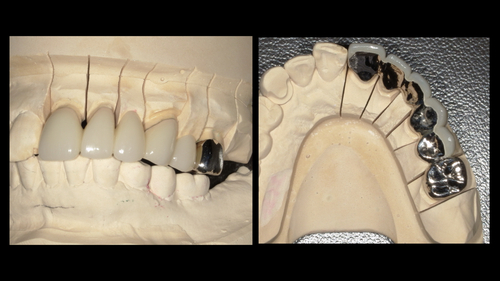

④抜歯と仮歯のセット

残念ながら保存することが不可能な左上1番目の歯の抜歯を行いました。同日にブリッジの土台となる歯も削り、仮歯をセットしました。今回はより長い期間ブリッジが安定するように右上の3番目から左上の3番目の歯までを土台とすることにしました。(どこまでの歯をブリッジの土台にするかは周囲の歯の状態や噛み合わせなどで判断が必要です。)

最終的な型取りを行いました。

⑦セット

型取りから2週間ほどでジルコニアセラミックブリッジが完成してきました。